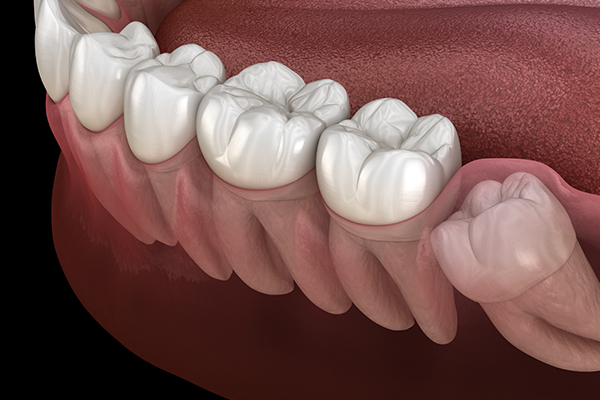

Some wisdom teeth erupt normally, but others may erupt at an angle, horizontally, or remain fully impacted. Wisdom teeth that do not erupt properly can disturb the dental arch and are difficult to clean, which may lead to decay of adjacent molars. In such cases, extraction is recommended.

• Horizontally

impacted wisdom tooth

• Angulated

• Vertically